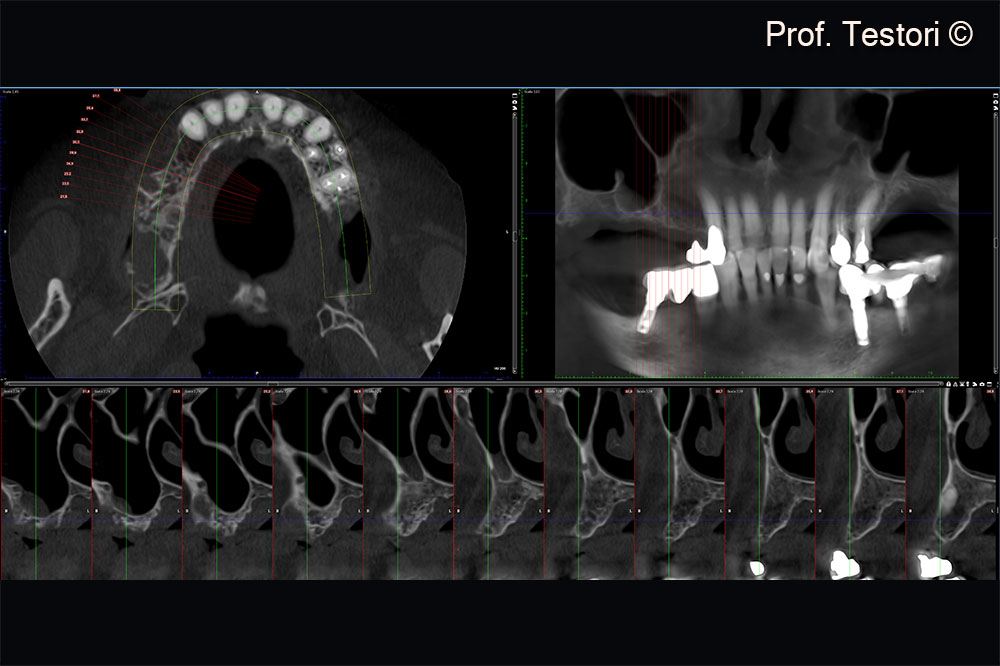

Radiographic evaluation at consultation visit.